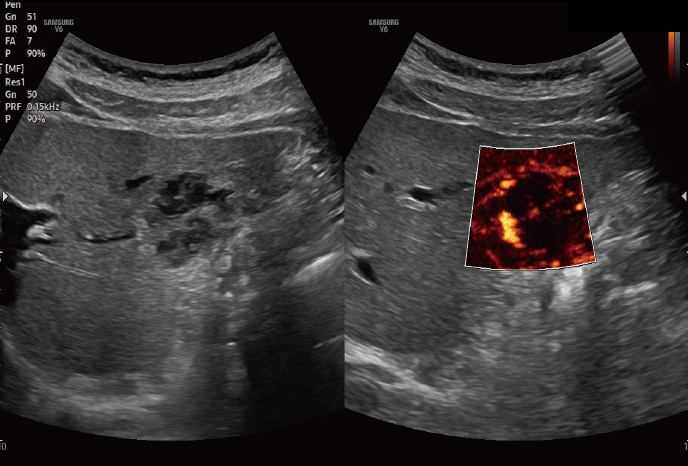

하이앤드 초음파 장비를

활용한 정밀 심장 검사

심장 질환 진단에서 가장 중요한 것은 ‘심장의 상태를 얼마나 정확하게 볼 수 있느냐’입니다. 저희 센터는 대학병원급 하이앤드 초음파 장비를 도입하여, 실시간 3D 렌더링으로 정밀 진단이 가능하며, 심장의 구조·혈류·기능을 실시간 고해상도로 관찰합니다.

미세한 판막 움직임, 혈류 속도 변화, 심방·심실 크기와 수축력까지 정밀하게 분석할 수 있어, 심장질환의 조기 발견과 치료 계획 수립에 큰 차이를 만듭니다.